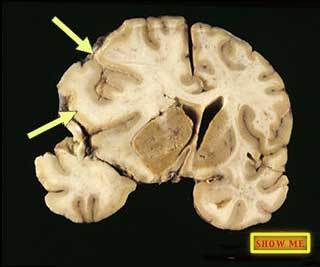

Can you find indications of some of the brain swelling that was responsible for her death?